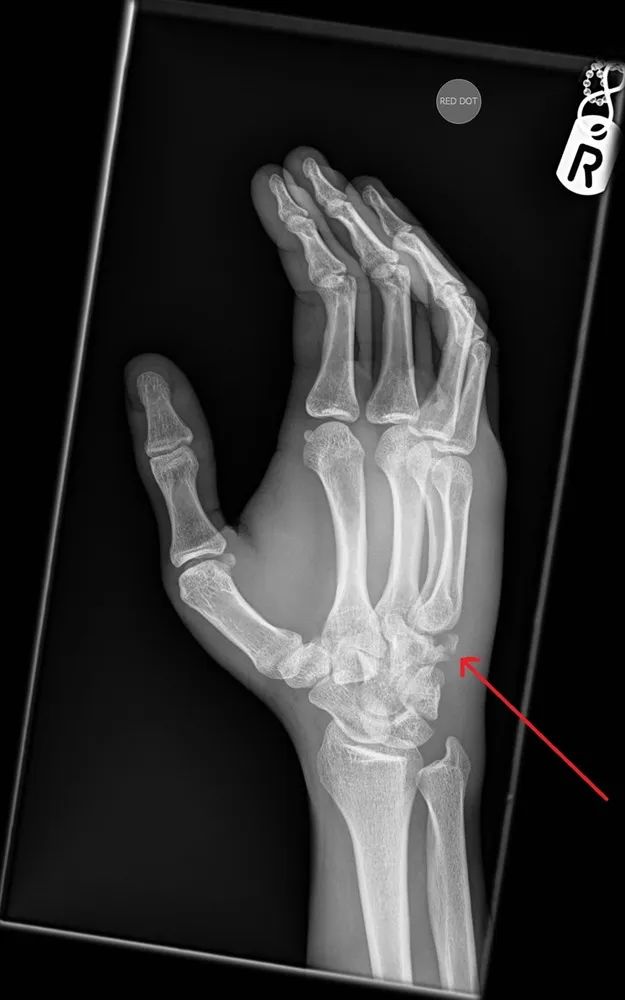

X线检查:正侧位均未发现骨折。因为患者第五掌骨底部与腕掌关节有压痛,故加做侧位片,如下图所示。

把这幅示意图发上来,大家进一步看一看。

右手斜位片,红色箭头提示钩骨骨折。